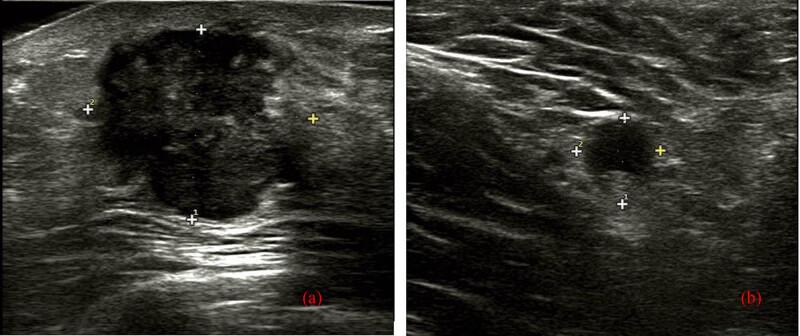

Metaplastic matrix-producing breast carcinoma is a type of metaplastic breast carcinoma (MBC), which is a rare malignancy, accounting for 0.2-1% of breast carcinomas. A 52-year-old female visited a hospital because of a palpable painless mass in the right breast and was diagnosed with Breast Imaging Reporting and Data System (BI-RADS) category 4A via ultrasound (US) with a suspected positive lymph node at the right axillary region. Excision of the breast mass was performed and histopathologically confirmed that it was MBC with osseous differentiation. No distant metastasis was revealed before a modified radical mastectomy; however, metastasis to a lymph node of the right axillary region was observed (1/22). She received six cycles of TEC scheme chemotherapy (docetaxel, epirubicin, and cyclophosphamide, 21 days) and 5 weeks of radiotherapy (48 Gy/25 f/5 days a week), but without any follow-up examinations since radiotherapy. Twenty-four months after surgery, distant metastases to lungs and liver were confirmed and died 3 months later. This case provides valuable information for clinicians on MBC and suggests that further examination or biopsy should be performed to US BI-RADS 4A masses before surgery. In addition, regular postoperative follow-up plays important roles in detecting metastases early and improving prognosis.

化生型产基质乳腺癌是一种化生型乳腺癌(MBC),这是一种罕见的恶性肿瘤,占乳腺癌的0.2%-1%。一名52岁女性因右侧乳房可触及无痛性肿块就诊,经超声(US)检查诊断为乳腺影像报告和数据系统(BI-RADS)4A类,右侧腋窝区域可疑淋巴结阳性。对乳房肿块进行了切除,组织病理学证实为伴有骨分化的MBC。在改良根治性乳房切除术前未发现远处转移;然而,观察到右侧腋窝区域淋巴结转移(1/22)。她接受了六个周期的TEC方案化疗(多西他赛、表柔比星和环磷酰胺,21天)和5周的放疗(48 Gy/25 f/每周5天),但自放疗后未进行任何随访检查。术后24个月,证实发生肺和肝远处转移,3个月后死亡。该病例为临床医生提供了有关MBC的有价值信息,并表明在手术前应对US BI-RADS 4A类肿块进行进一步检查或活检。此外,定期术后随访在早期发现转移和改善预后方面发挥着重要作用。